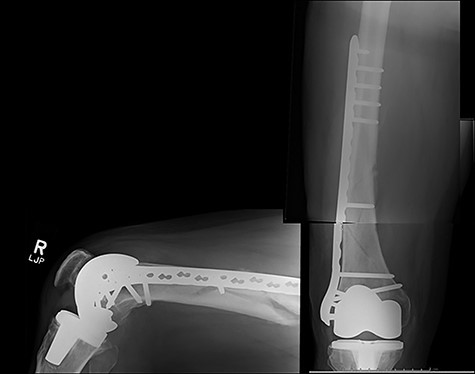

The cases of failure are here examined in more detail. Case 1 (Figs 1 and 2): this active gentleman was paddleboarding off the Llŷn peninsula when he was knocked onto his side by a wave.

Fracture above plate tip following successful union for Case 1.

Clearly, this has occurred following on from successful union. Despite a sound original fixation, the rigid construct has acted as a lever-arm to produce a fracture above the plate tip. In long spiral fracture configurations such as this, antegrade intra-medullary nailing could be considered as the primary treatment modality.